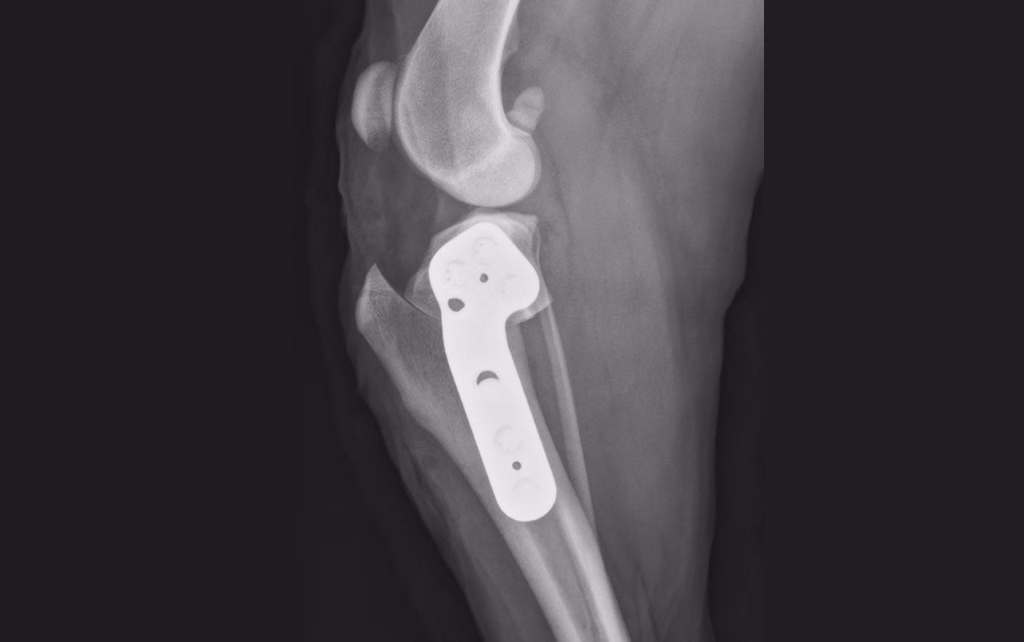

- Chirurgisch: als de kruisband volledig gescheurd is of wanneer niet-chirurgische behandeling onvoldoende effect heeft. Technieken zoals TTA (Tibial Tuberosity Advancement), TTA Rapid, TPLO en kunstband/teugel (“Flo-teugel”) worden gebruikt om de knie te stabiliseren.